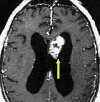

Удаление опухоли мозжечка и IV желудочка

Удаление опухоли из мозжечка и IV желудочка выполняется для предотвращения или устранения окклюзионной гидроцефалии в результате оттока поврежденной спинномозговой жидкости, сопровождающейся смещением мозжечка и ствола головного мозга в затылочное отверстие и сдавливанием. Если невозможно радикально удалить новообразование, его частично иссекают или декомпрессию задней черепной ямки выполняют путем резекции I дуги шейного позвонка и края затылочного отверстия. Если невозможно восстановить отток спинномозговой жидкости во время хирургического вмешательства, используется операция шунтирования: вентрикулостомия третьего желудочка, анастомоз четвертого желудочка с мозжечково-мозговым резервуаром, боковой дренаж бокового желудочка.